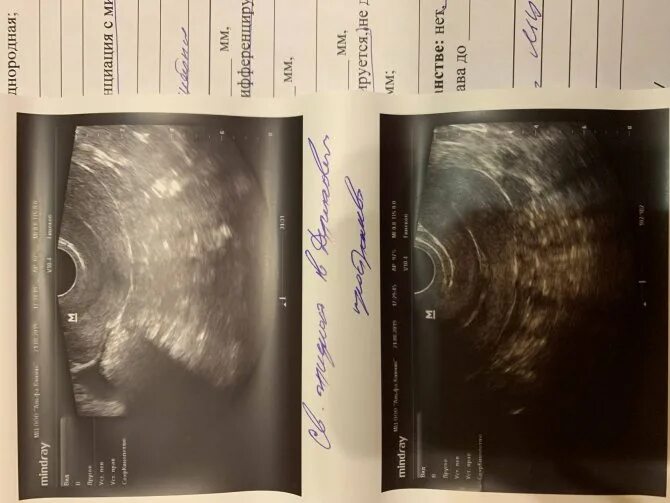

Позадиматочное пространство